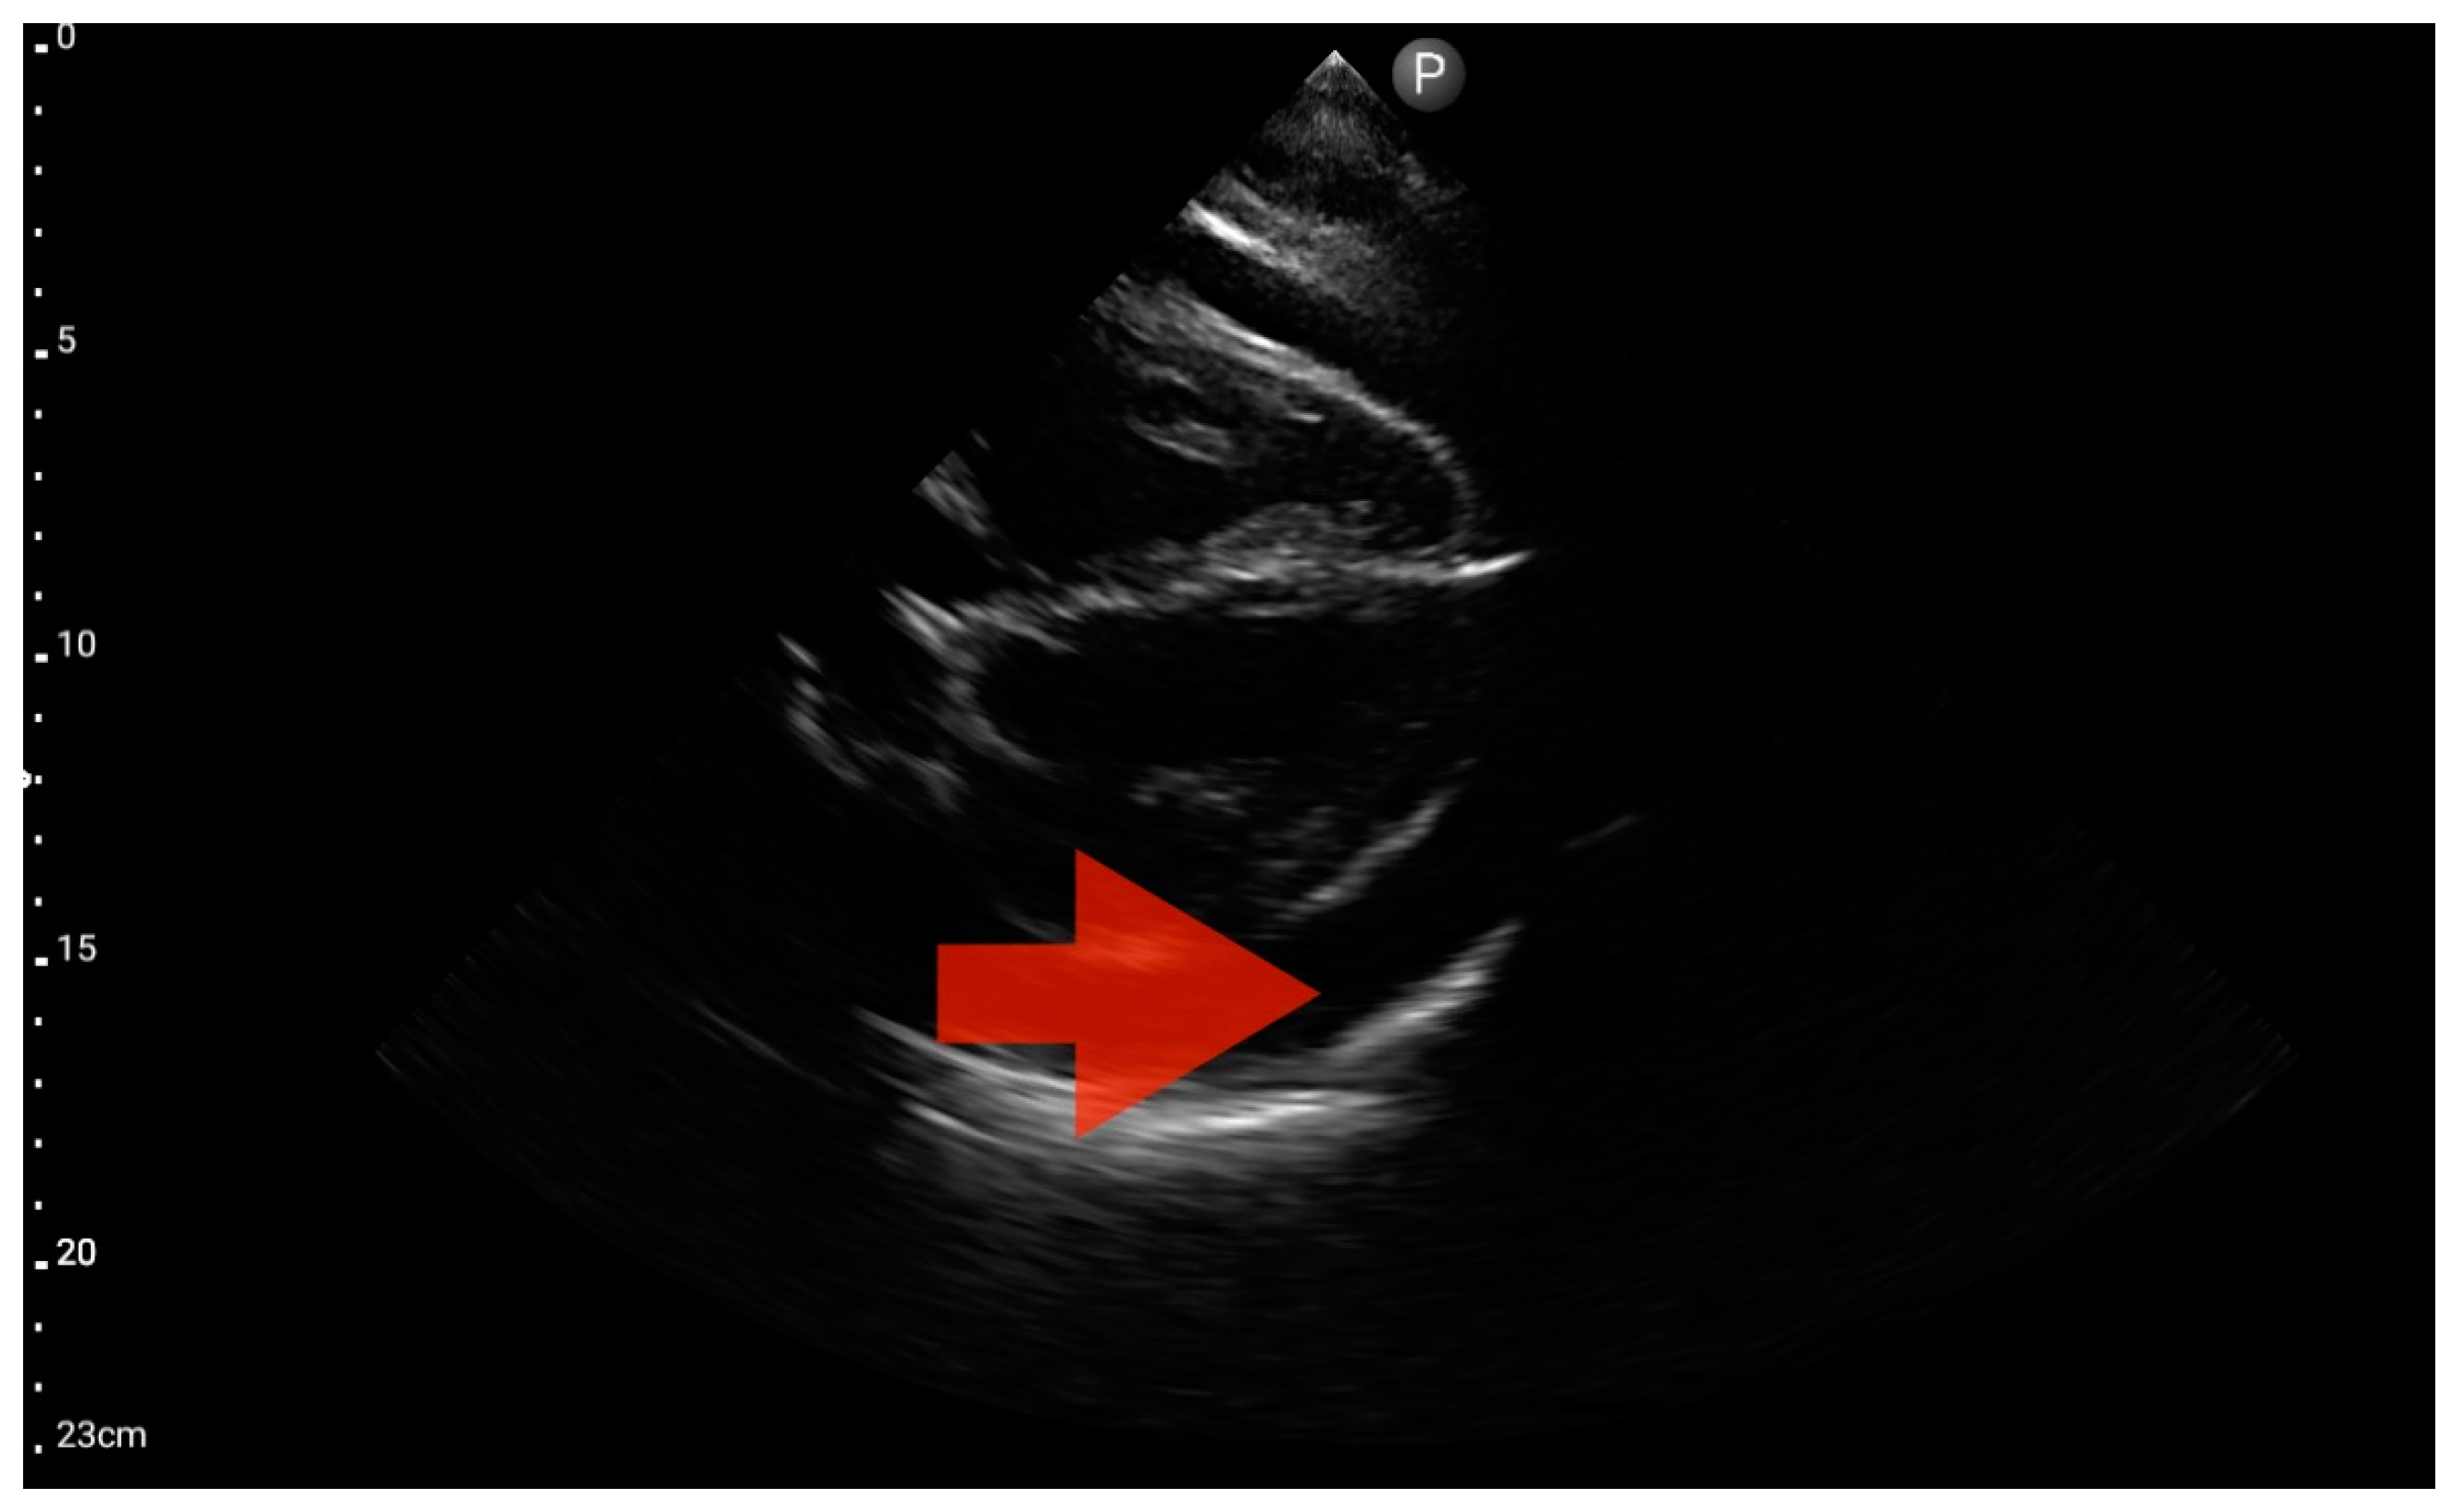

Figure 11.

Pleural effusion (BLUE protocol). Convex probe examination, the basal part of the lung (pleural recess); the red arrow indicates free fluid in the pleural cavity (source: author’s material—DK).

3.4. The Assessment According to the FATE Protocol

Left ventricle hypokinesis, identified through the FATE protocol (Figure 11), was deemed the most valuable information. This observation exhibited a significant association with the hospital-established diagnosis of decompensated heart failure as the primary cause of patient-reported dyspnea. The sensitivity and specificity were 1.0 (95%CI: 0.62–1.0) and 0.6 (95%CI: 0.15–0.95), respectively. The positive predictive value was 0.85 (95%CI: 0.55–0.98), and the diagnostic accuracy was 0.86 (95%CI: 0.62–0.98).